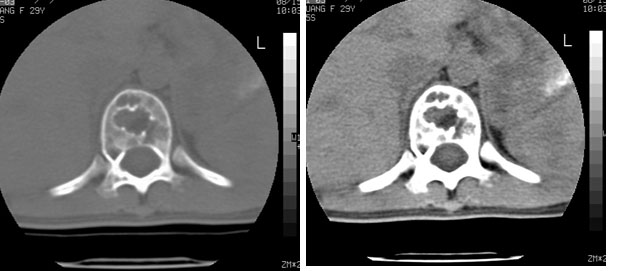

考虑多发骨髓瘤可能性大。(骨松质内弥漫性分布,边缘清晰的溶骨性破坏,无硬化。睥脏增大,其内有多个圆形底密度影。淋巴瘤不除。

脾及椎体多发占位病变.

脾脏及椎体多发占位病变。首先考虑淋巴瘤,其次骨髓瘤。建议查本周氏蛋白

2/t12压缩性骨折。脾挫裂伤(建议继续扫描或b超检查)

椎体多发性溶骨性破坏,部分融合,椎旁无软组织肿块、椎间隙正常,t12 压缩,脾脏增大,其内示多发低密度影,首先考虑多发性骨髓瘤。病人较年轻,平素无异常,转移瘤可能性小。